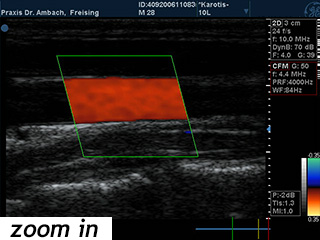

Gefäßdoppler

Mit Hilfe des Ultraschalls können unter Anwendung der Doppleruntersuchung und der Farbcodierung des Blutflusses die verschiedenen Gefäße des Körpers untersucht werden: Zum Beispiel die Halsschlagadern (Carotiden), die Bauchschlagader (Aorta abdominalis), die Nierenarterien, die Beingefäße etc. Die Darstellung der Nierengefäße dient der Abklärung eines hohen Blutdrucks. Mit der Untersuchung der hirnversorgenden Gefäße können Verengungen oder Verkalkungen beurteilt werden, sie kann außerdem auch Hinweise auf eine möglicherweise gleichzeitig bestehende Herzerkrankung geben.